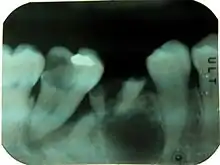

Periapical readiograph of lower right teeth, showing a large carious lesion in the distal of the lower right second molar. The same tooth also has an extensive periodontal defect. At this stage, without further information, it is difficult to tell which process has occurred first and lead to the death of the pulp.